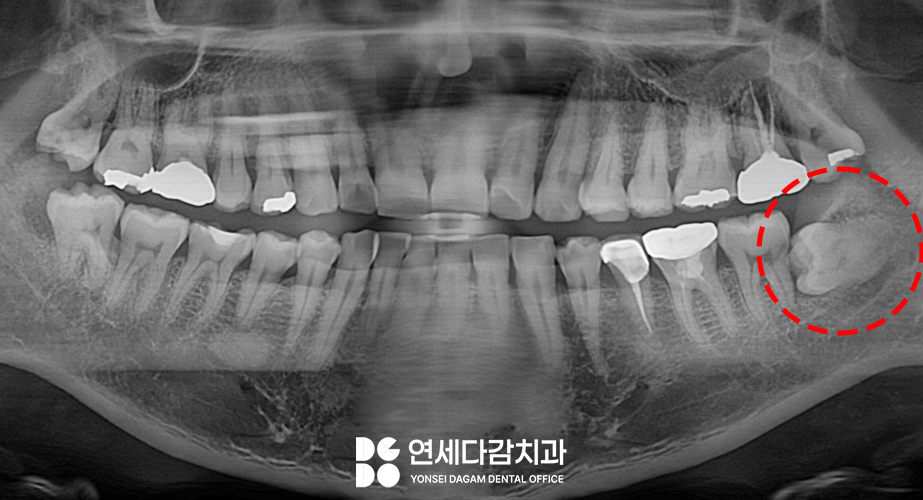

오금역 치과 에서

파노라마 사진에

표시한 부위를 보면

수평으로 매복되어 있는

형태였는데요.

이를 빼기 전 정확한 진단을 위해서

CT를 촬영하여 주위 구조를

3차원적으로 분석합니다.

CBCT 분석 결과

신경관이랑 근접해 있습니다.